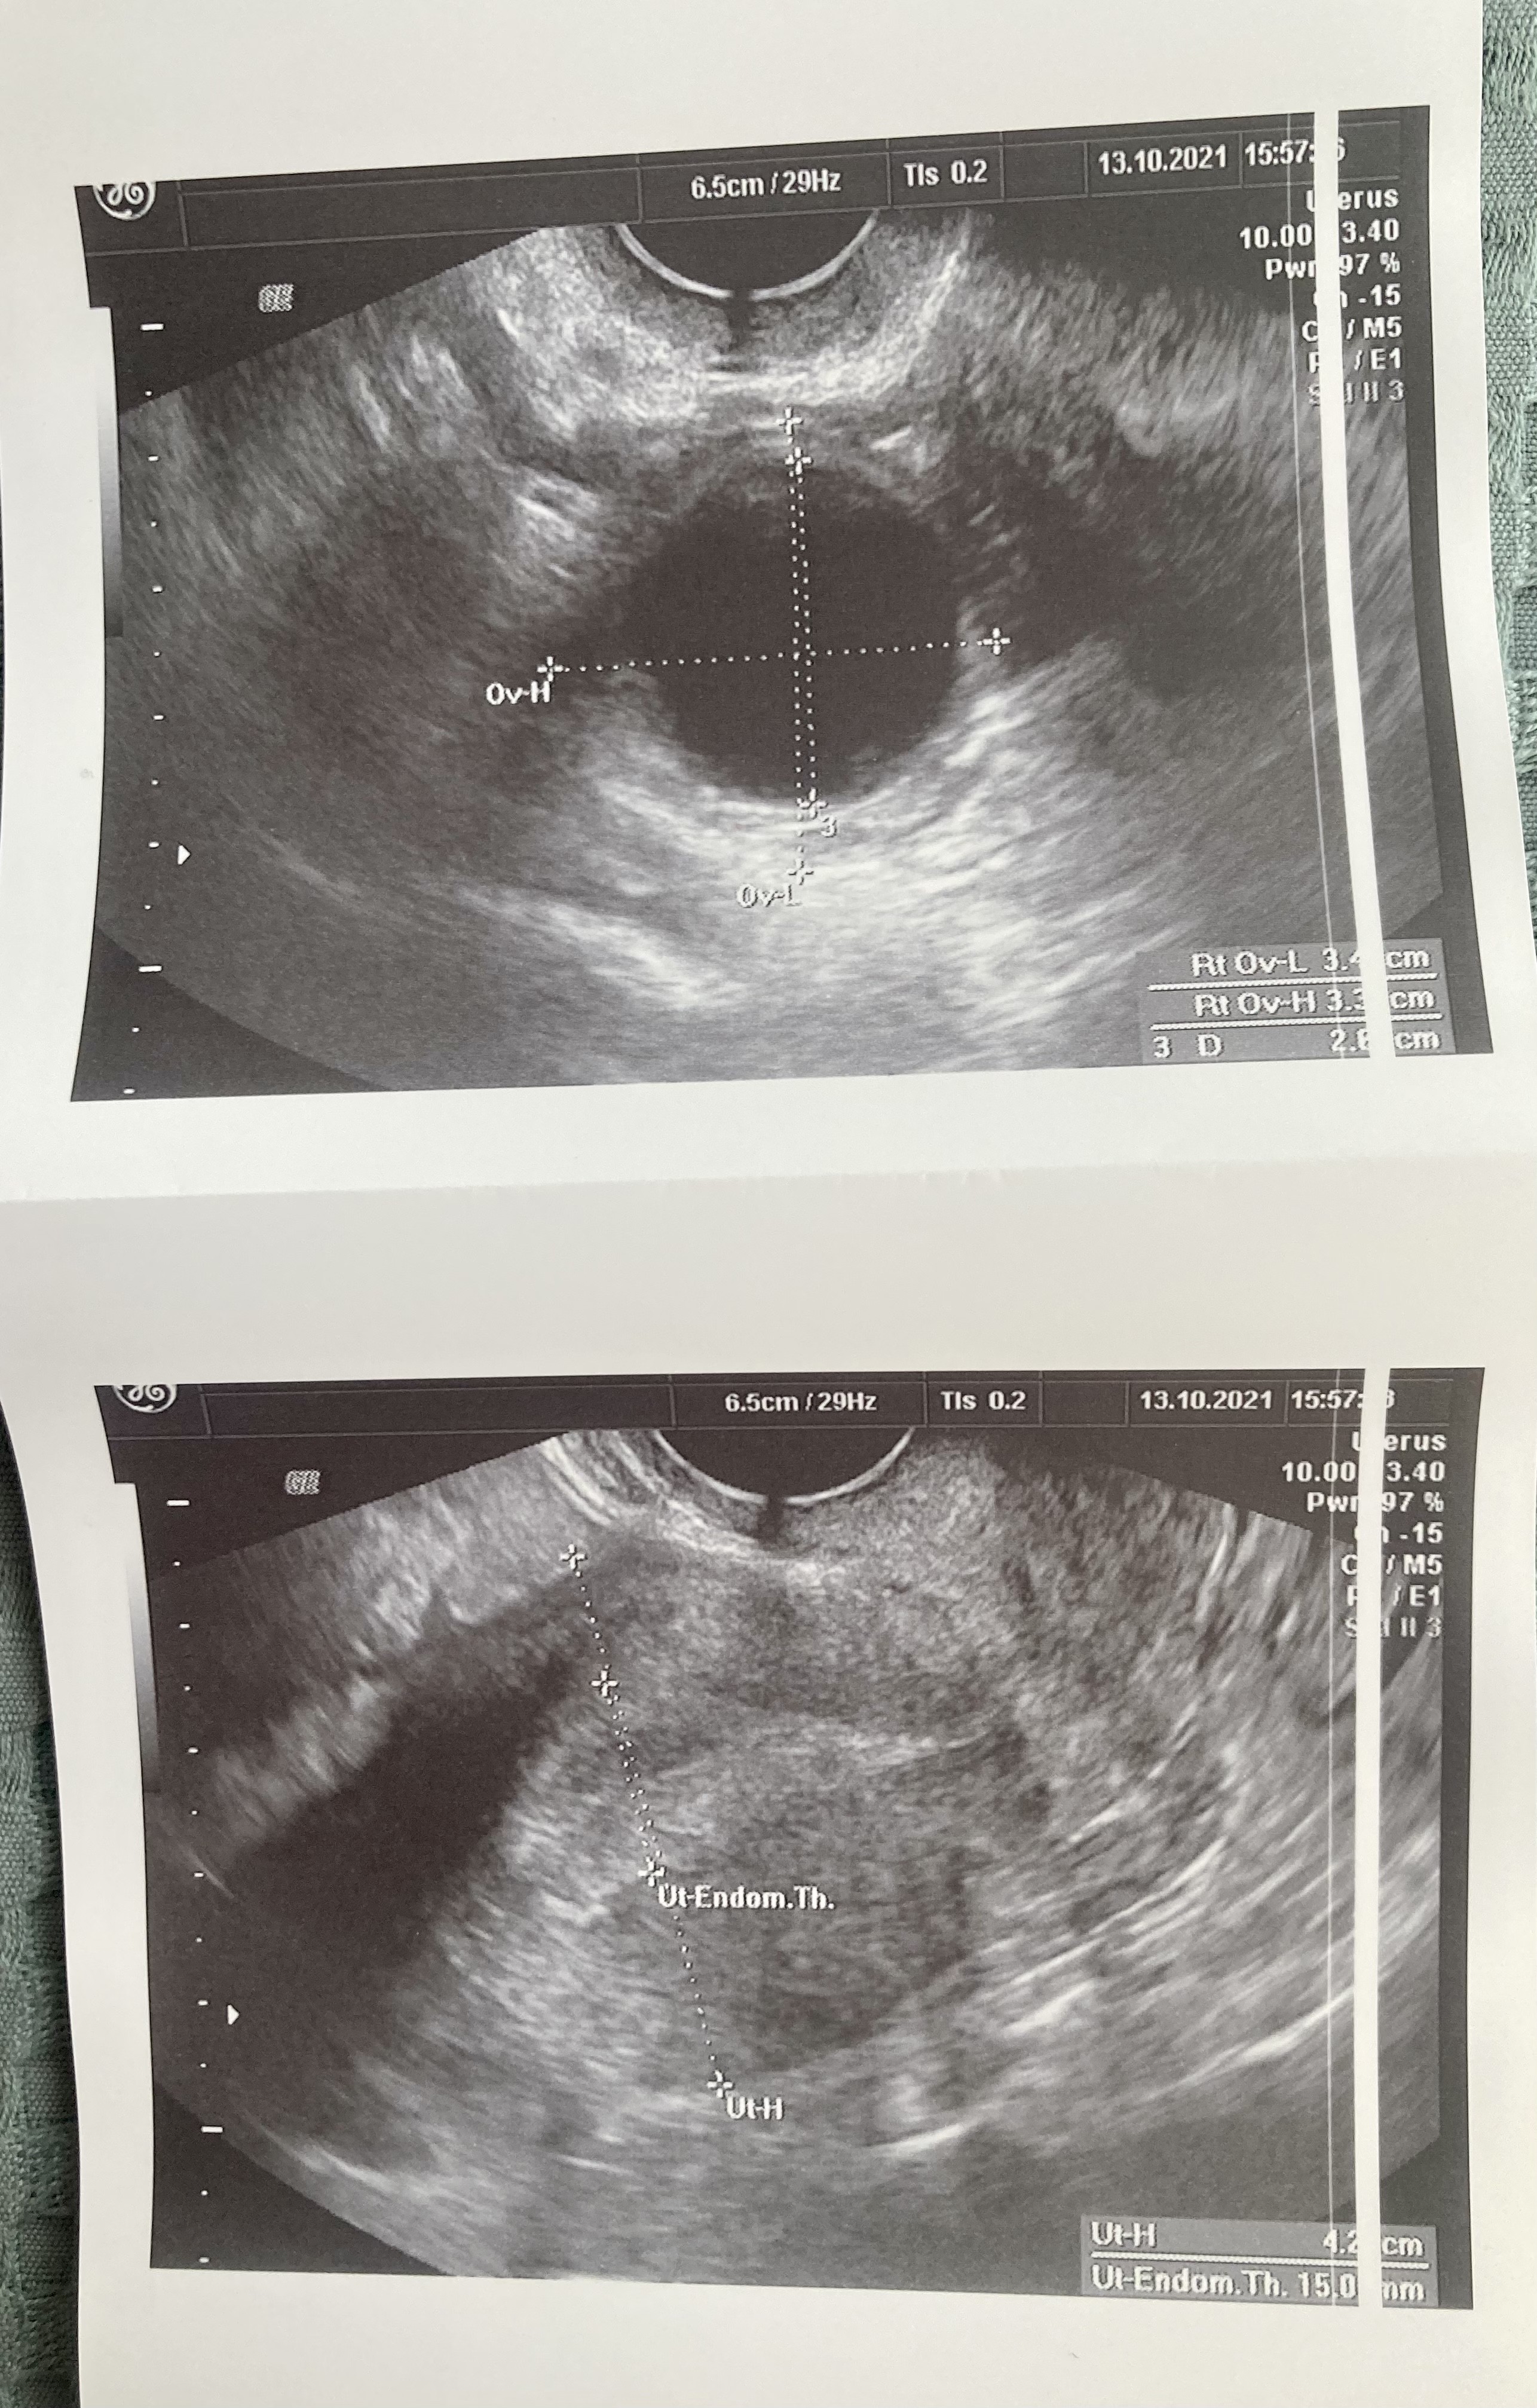

Co więcej, właśnie wyciągnęłam zapis usg i wychodzi, ze ta torbiel ma 6,5cm a nie 3,5 🙈 nie za bardzo ogarniam obraz na usg, ale jak w mordę strzelił jest 6,5cm.

• F3411FB7-F7D6-444A-8127-AECC3D6B5334.jpeg

F3411FB7-F7D6-444A-8127-AECC3D6B5334.jpeg

2 MB · Wyświetleń: 88

• 90716A2F-7AC1-4AE4-927A-0776D9432447.jpeg

90716A2F-7AC1-4AE4-927A-0776D9432447.jpeg

2 MB · Wyświetleń: 89

• 33DED63C-B319-4B06-8ED9-AB1C7413B1AC.jpeg

33DED63C-B319-4B06-8ED9-AB1C7413B1AC.jpeg

1,2 MB · Wyświetleń: 86